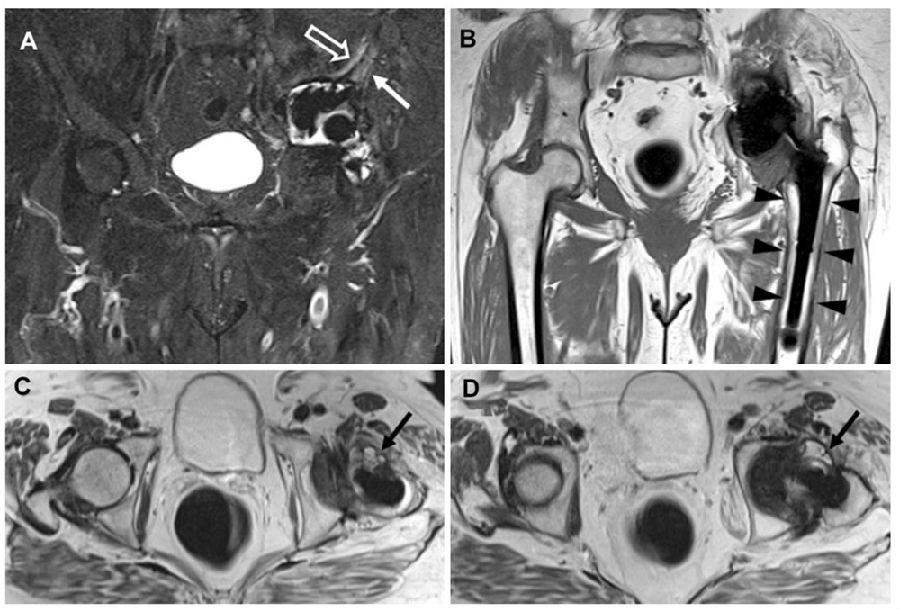

人工智能方法有助于关节置换术后PJI术前手术计划、感染的早期诊断、早期使用合适的抗生素以及预测临床结果等。wu等[20]研究证实,人工智能可以用于自动检测复杂的切口部位感染。Albano等 [21]研究人工智能是否可以根据术前MRI特征区分出拟翻修的全髋关节置换术是否存在化脓性感染可能。作者纳入173例(98 名女性,年龄:67±12岁)THA 翻修手术患者术前骨盆MRI影像资料,患者分为训练、验证、内部测试组(n=117)和独立的外部测试组(n=56)。MRI影像特征用于训练、验证和测试基于支持向量机(SVM)的人工智能算法。结果发现,第一组中,人工智能算法在预测THA感染敏感性达到92% 、特异性为62%,AUC为81% 。在外部测试组中,人工智能预测THA感染敏感性达到92% 、特异性为79%,AUC为89%。作者认为, 使用基于支持向量机的人工智能算法读取MRI影像特征在预测THA术后感染方面是一个很有希望的方法。该模型可能有助于放射科医生识别THA术后感染(图9)。

图9 一名77岁THA感染女性的骨盆MRI

冠状STIR(A)显示假体周围髋臼骨水肿(白色箭头)和囊外水肿(空心箭头)。冠状T1加权图像(B)中未发现骨破坏。轴位T2加权图像(C和D)显示炎症和滑膜炎